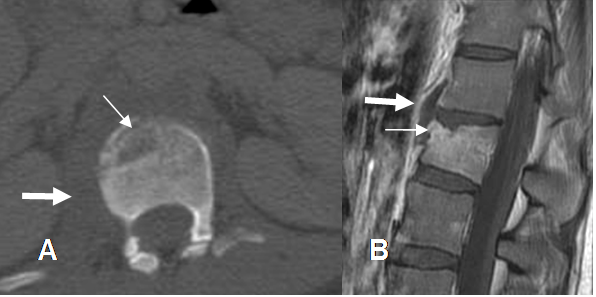

Fig 50. Osteomielitis TBC.

A: TAC axial y B: RM sagital en T1 con contraste. Pérdida de altura y lesión osteolítica en la parte anterior del cuerpo vertebral, que realza con el contraste por osteomielitis. Prominencia de los tejidos blandos para espinales, por extensión de la infección. (Flecha gruesa).